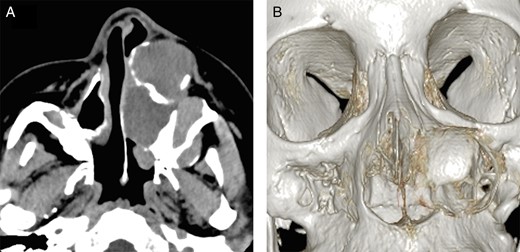

Physical examination revealed a non-tender, hard swelling of the left nasal wing from which serosanguineous fluid was aspirated by fine needle (Fig. 1). Intraoral examination showed a soft palatal expansion and on panoramic radiography, the identified cyst had no relation to the neighbouring teeth. Computed tomography showed a trilocular cyst in the left maxillary region (Fig. 2). A clinical diagnosis of surgical ciliated cyst was made, and facial osteotomy and cyst enucleation were performed under general anaesthesia. Lateral rhinotomy provided excellent exposure of the expanded cortical bone, which was removed carefully with a bone chisel. Serosanguineous fluid filled the cyst cavity just below the surface; however, palatal and nasal cyst cavities contained straw-coloured fluid. The cyst was enucleated, and the facial wound was closed primarily (Fig. 3). Healing was uneventful. Histopathological examination showed that all cyst walls were lined by ciliated columnar epithelium, which was consistent with surgical ciliated cyst (Fig. 4). The patient showed no signs of recurrence at the end of a 20-month follow-up, and the postoperative appearance was excellent (Fig. 5).

Computed tomographic appearance. (A) Axial computed tomographic section showed a well-defined trilocular cyst in the left maxillary region extending to the cortical plate. (B) Three-dimensional computed tomographic image showing a defect in the nasal lateral wall.